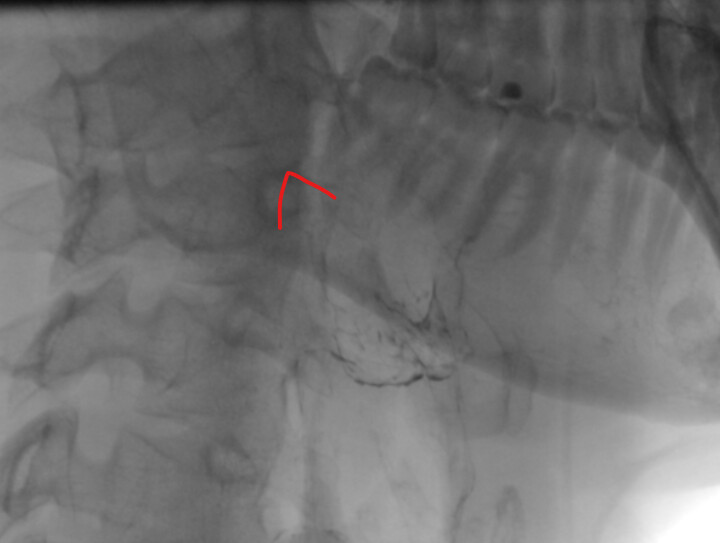

I also have some images from 2021 (taken during an investigation for dysphagia/pharyngeal pouch) which I think may show an elongated styloid. However, I’m not sure if I’m actually seeing something significant, or if it’s just artefact/normal anatomy.

I’ve also included a front-on image and highlighted around the bit that I think shows the styloid process. Is that it, or something else?

@carl - OOPS! Sorry about that! I added the image I annotated to my previous post. I can faintly see the styloid you outlined. Getting a CT scan w/ contrast as previously mentioned will be the best way to see how your styloid may be playing into your symptoms, especially the vascular ones.